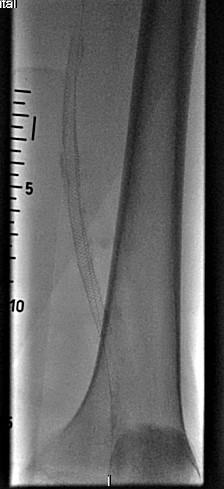

Они провели пациенту высокотехнологичную малоинвазивную операцию по восстановлению проходимости артерии − баллонную ангиопластику и стентирование. После операции просвет артерии восстановился – пациенту удалось сохранить ногу. Более того, ходить он может теперь долго и без боли, а значит, человеку вернули активную полноценную жизнь.

Как отмечают хирурги областной больницы, на протяжении десятков лет открытые операции по восстановлению проходимости сосудов оставались "золотым стандартом" в лечении пациентов с критической ишемией нижних конечностей. За последнее время стратегия лечения таких пациентов в ИОКБ претерпела значительные изменения, в первую очередь за счет усовершенствования качества эндоваскулярных расходных материалов и высокой квалификации врачей.